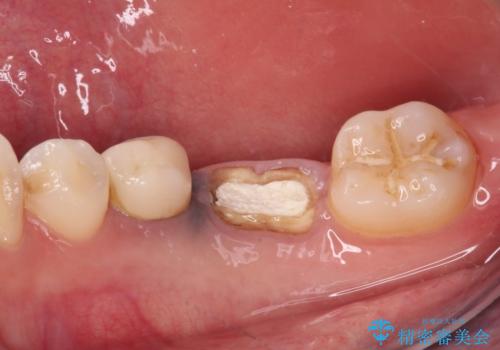

- 他院で治療を開始したものの抜歯が必要と言われ、何とか残せないものかとのことで来院された患者様です。

下顎大臼歯は歯冠部分が残っておらず、保存が難しいように思えましたが、まずは根管治療を行った上で補綴治療を行うこととしました。

上顎臼歯は、おそらく銀歯を外して仮詰めされていたため、再度形を整え、セラミックインレーにて修復治療を行うこととしました。